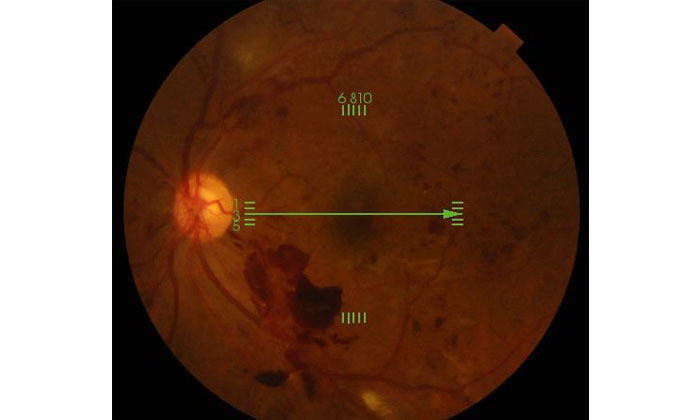

血糖値が高いと、血管がもろくなり血液成分が漏れ出し、網膜に出血や視力を司る黄斑部に浮腫(水膨れ)が生じ視力が低下する病気です。悪い血管(新生血管)が出てきたり、さらに悪化すると増殖膜(普通にはない膜)が発生し、網膜を引っ張り網膜剥離に至ることもあります。							症状は初期は無症状ですが、網膜病変が進行するにつれ視力が低下します。硝子体内に出血すると一気に見えなくなることもあります。緑内障を合併してくることもあります。							治療は、初期はレーザー治療や抗VEGF療法という目に注射をします。網膜剥離などに至ると外科的手術治療になります。